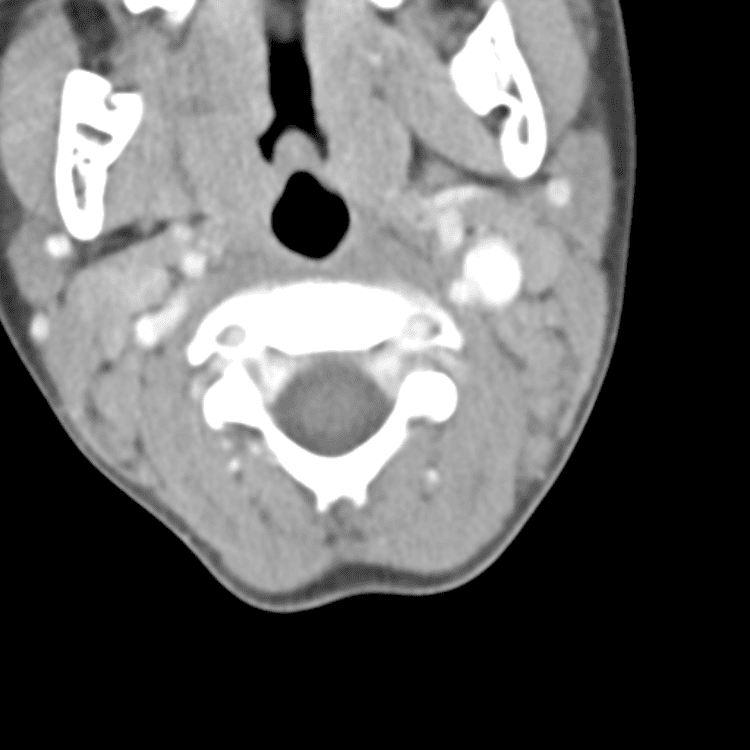

Head and Neck

Simulates call by including subtle or difficult cases and some normals.